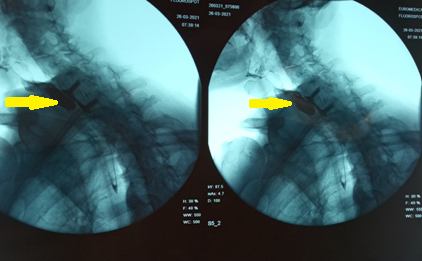

White arrows indicate the leak from the posterior esophageal wall (Courtesy Dr. V. Penopoulos)